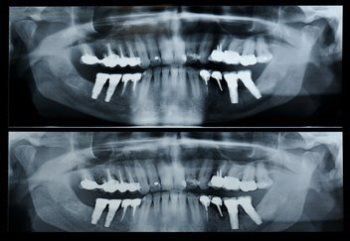

Panorex

A panorex is a very impressive piece of imaging machinery in which, once positioned in the machine, it will rotate around your entire head taking a full 360 degree view of the teeth, head, sinuses and bones. The image is used to evaluate the health of the imaged structures, and to aid in treatment planning your dental care.